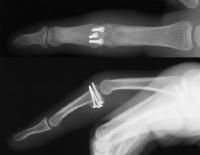

In the operating room, the crushed bone is removed and provisional fixation of the volar graft is obtained with Kirschner wires.

These wires are then replace, one at a time with micro screws.

Here, the graft is in place and the joint has been reduced. The proximal two screws were then backed out slightly, and the volar plate was secured with sutures looped around the proximal two screws, which were then tightened back (not shown).

Final reconstruction.